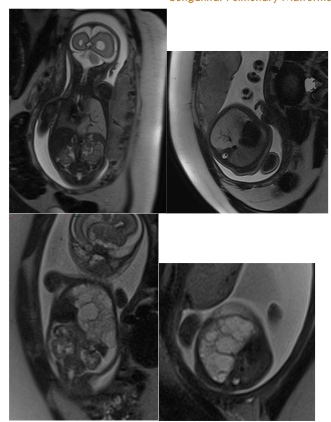

With the advent and widespread use of prenatal ultrasound, it has become possible to detect these malformations as early as 18–20 weeks of gestation. Additionally, fetal magnetic resonance imaging (fetal MRI) has emerged as a valuable complementary tool, providing detailed information about CPMs without the need for contrast agents. It allows for assessment of the size and internal characteristics of the lesion (solid, cystic, or mixed), the presence and course of abnormal vessels from both the pulmonary hilum and systemic circulation, and estimation of the volume of healthy residual lung parenchyma.

Figure 2. Congenital pulmonary malformations with large and small cystic areas of hyperinflation. No systemic irrigation was observed.